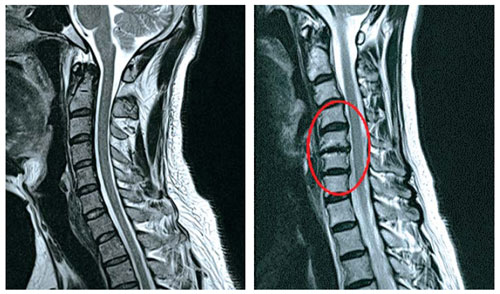

목 디스크는 목의 디스크(경추 디스크)에서 출현하는 질환으로, 경추 디스크 사이의 연골판이 터져 디스크 내부 물질이 경추 신경을 자극해 통증이나 저림증 등의 증상을 유발 해요. 목 디스크는 일상생활에서의 안 좋은 자세나 많은 운동, 부상 등이 이유가 되는 것이 될 수 있기도하고, 시간이 지날수록 발생 확률이 높아져요. 목 디스크의 증상으로는 목 부위의 통증, 팔의 저림, 근육 약화 등이 있으며, 증상이 난폭한 경우 수술 등의 치료가 필요할 수 있어요. 그리하나 대개의 경우 치료 없이도 시간이 지나면 증상이 호전되는 경우가 대부분입니다.

추간판의 수핵이 빠지거나 퇴행성 경추증 및 경추관협착증 등으로 척수가 압박되면 대다수 팔에 힘이 빠지는 것을 느끼게 돼요. 척수가 눌리는 정도이기 때문에 한쪽 팔만 마비될 수 있고요. 하지마는 양팔의 감각이 둔해지고 눈을 감고도 어지럽기 때문에 이러한 목 디스크 증상이 나타나면 무척 위험한 상태가 되기 때문에 빨리 치료가 필요해요.

척수라는 중추 신경은 목뼈를 통과해 목 아래 감각과 운동 신경에 영향을 끼치기 때문에 목 디스크 증상들이 나타나면 신속하고 빠른 대처가 필요해요. 목디스크 치료형식으로 주로 초기 스탭에는 물리치료나 약물을 통해 대개의 환자들이 호전돼요. 그렇지 않다고 하면 신경 성형술과 차단술이라고 부르는 뼈주사 목디스크 치료방법을 이용하는데, 이 치료방법은 통증이 있는 신경 부위에 약물을 삽입하는 것입니다.

시술로써 눈에 띄게 질환을 현저히 치료하시는 것이 아니라 염증을 보완하고 통증을 낮추는 것이 포인트입니다. 이러한 방식으로 비 수술적인 치료를 3개월 이상 넘었음에도 불구하며 증상이 호전을 보이지 않으신다면 목디스크 치료방법 중 수술적 치료를 고심해야 하더라고요. 인공디스크를 투입하기 위함으로 절개를 통하기에 디스크를 제거하며 뼈를 하나로 유합 시켜서하는 것과, 내시경 수술로 빠져 나온 수핵 자체만을 제거시켜서하는 방법이 있다고하고요.